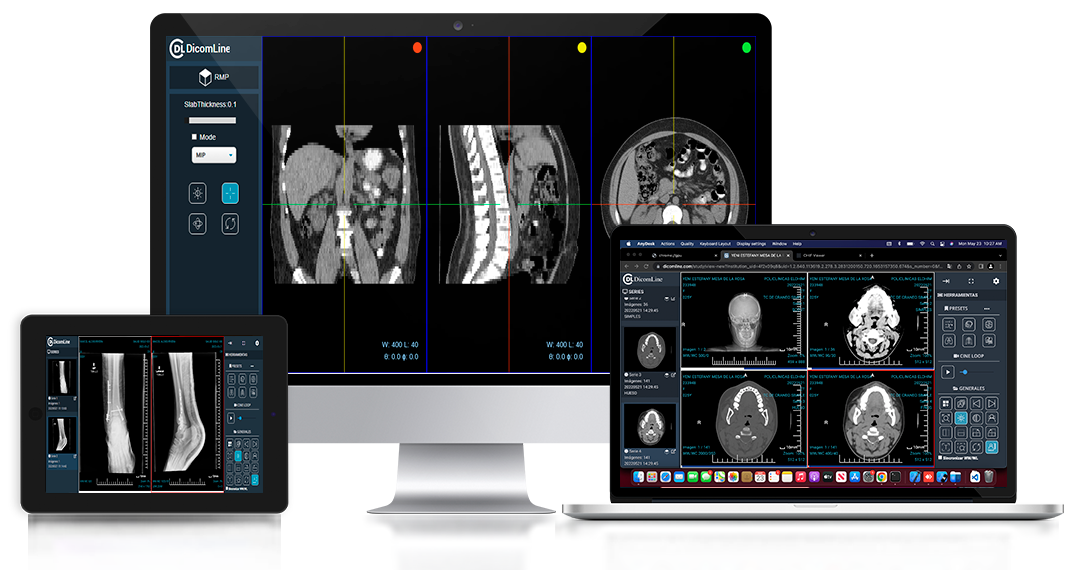

Acceso Universal

Accede a tus estudios desde cualquier lugar y dispositivo, sin instalaciones complicadas.

Arquitectura Cloud-Native

Diseñado 100% para la nube desde el primer día. No es un sistema tradicional "adaptado" para internet. Escalabilidad infinita, actualizaciones automáticas y acceso instantáneo desde cualquier lugar del mundo.

Experiencia de Usuario Superior

Interfaz intuitiva diseñada por médicos para médicos. Flujos de trabajo optimizados que reducen clicks, tiempo de carga ultra-rápido y herramientas que se adaptan a tu manera de trabajar.